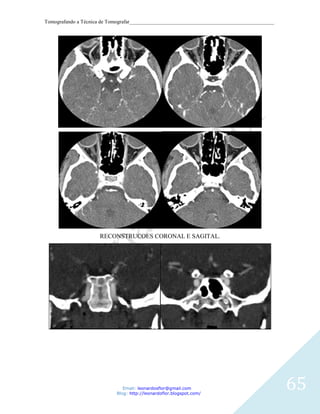

RECONSTRUCOES CORONAL E SAGITAL.